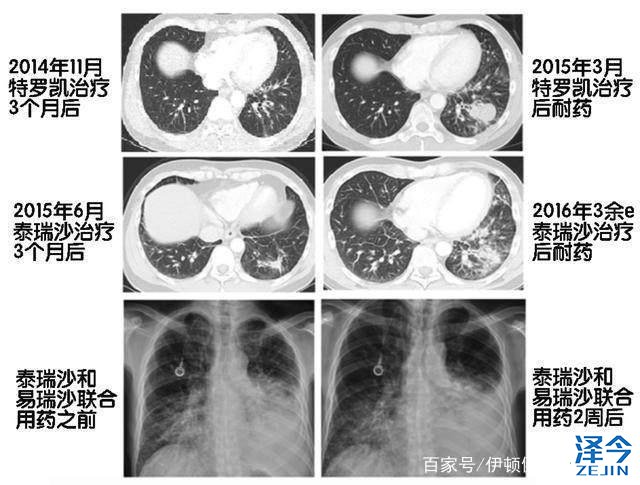

一位40多岁的非小细胞肺癌患者、2014年中旬就诊时发现在骨头和纵膈有转移灶,随后、基因检测验证患者EGFR基因的19号外显子存在缺失突变,患者遂服用特罗凯予以治疗,有效控制病情6个月后复发,活检中发现为T790M突变所致,改服泰瑞沙80毫克每日,病情稳定长达12个月后,患者因淋巴管炎症不得不转而使用卡铂和紫杉醇联合化疗,化疗至第四个疗程时,病情又有所进展,故而启用纳武单抗,单抗治疗四疗程后,因呼吸困难重做CT发现淋巴管炎加重,在脑、肝等处发现新转移病灶,由此开始使用培美曲塞化疗,然病情继续恶化。

最终、通过进行数字PCR检测发现了C797S基因突变,再次进行深度测序,发现T790M和C797S反式构型。于是、患者使用泰瑞沙(AZD9291)和易瑞沙的联合疗法,仅三天病症便有所好转,两周后咳嗽与呼吸困难得到控制,影像学检查也证实患者病情缓解,但至联合用药一个月后,病症重现、病情恶化,半月后患者离世。

患者的治疗过程图

该案例中患者使用泰瑞沙(AZD9291)联合易瑞沙后,总生存期仅为六周,通过对患者的两份血液样本分析,证实了患者携带的C797S癌细胞被联合用药方案予以压制,但在C797S突变丰度下降的同时,19del和T790M突变丰度却显著增加,从而导致了治疗的最终失败。